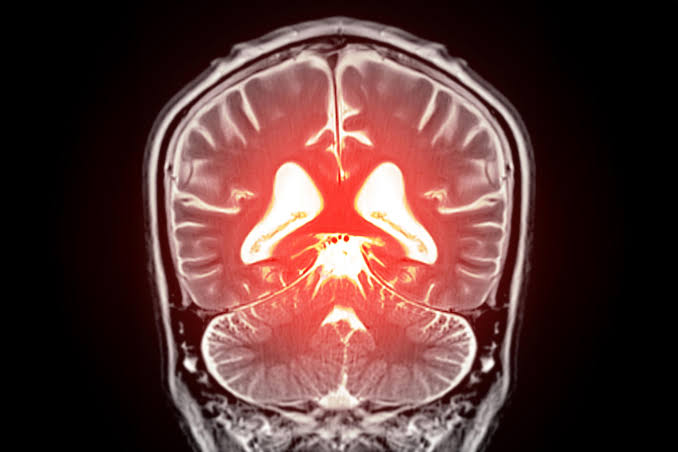

AI Could Detect Early Signs of Alzheimer’s in Under a Minute – Far Before Traditional Tests

Scientists are turning to AI and speech analysis to uncover early signs of Alzheimer's in ways traditional methods may miss. More than 7 million Americans...